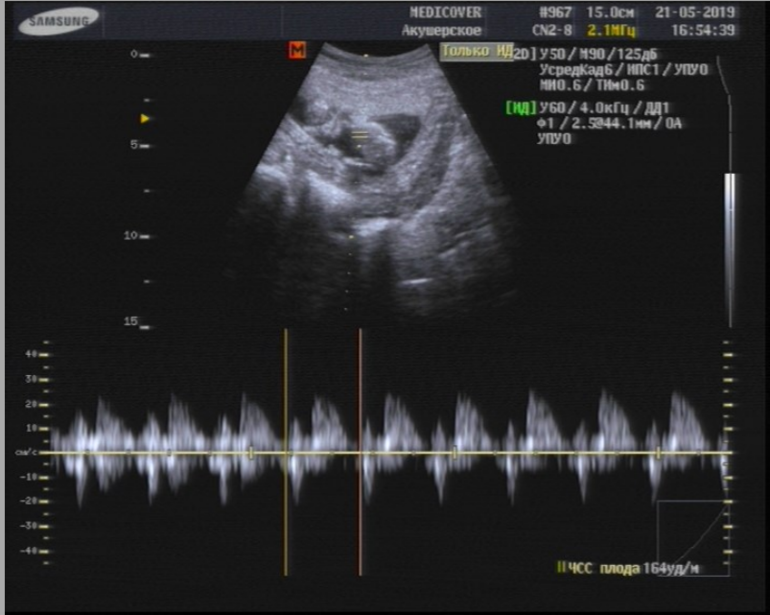

И какого же было мое удивление, когда я узнала, что УЗИ - входит в стоимость планового приема 😍 Я опять увидела свою ляльку! К гинекологу теперь - как на праздник! 😆 Муж правда расстроился, что пропустил такое мероприятие, если б знал что будет УЗИ - пошел бы со мной 😁 За две недели подросли на 2 см, врач говорит что все хорошо, развиваемся по сроку. Ребеночек и дальше активный, махал нам ручками, ножками, четко просматривались даже пальчики 😍 Пол разглядеть пока не получилось, врач предположил, что девочка, говорит "любят они прятаться" 😁 Даже сердечко не сразу получилось прослушать, не хотела поворачиваться как надо, но в итоге словили - 164 удары в минуту.

Ну и напоследок - фото. Опытные мамочки, видно что-то? Есть предположения? 😊